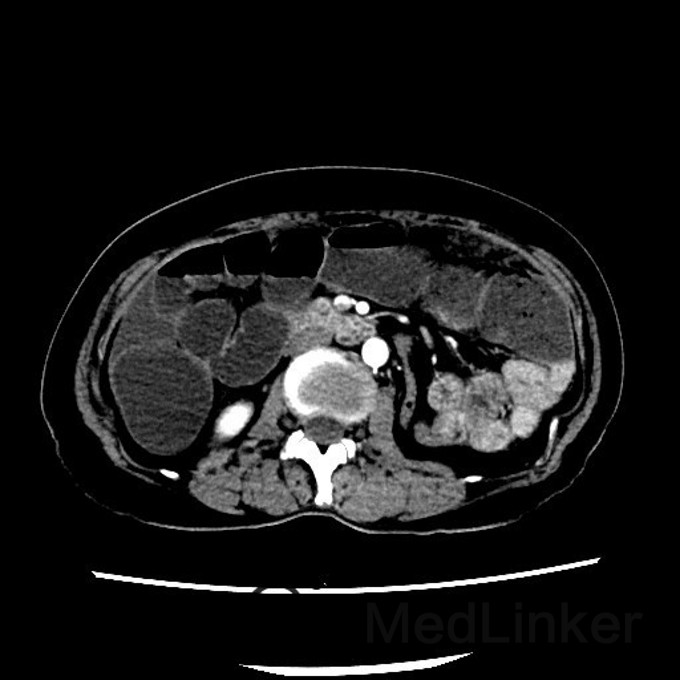

问题:患者女,50岁,因腹胀而就诊,遂行胸腹CT,提示:腹部大网膜、小网膜区脂肪间隙模糊,腹膜增厚,可见片絮状、小结节状软组织密度影,增强扫描见轻度强化。考虑转移癌可能性大。后行大网膜活检,病理结果提示:低分化转移癌。但全身PET/CT未见原发灶,此种情况下,常考虑原发灶在那些部位,以及进一步做什么检查?